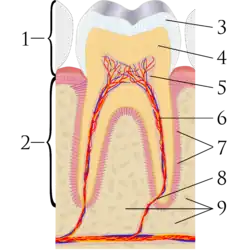

Teeth have a thin enamel layer on the outer surface. The enamel layer is whiter and semitransparent, and contributes blue, pink green tints to the tooth color.[6] The underlying dentin layer is darker than enamel, yellow-brown in color, and less transparent.[6] Dentin forms the bulk of the tooth substance,[7] and contributes most to the overall tooth color.[6] At the core of the tooth is soft connective tissue termed the dental pulp.[8] The pulp is pink/red due to its vascularity, but is rarely visible through the overlying enamel and dentin unless the thickness of these layers is reduced by tooth wear (or rarely internal resorption).